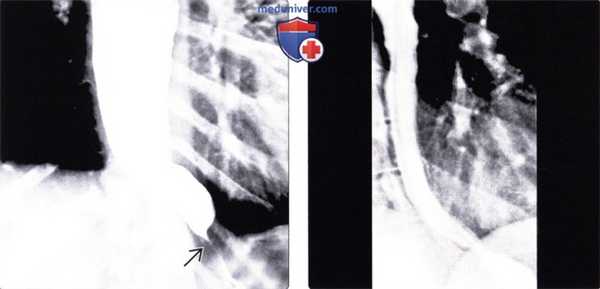

(Слева) На рисунке показана гипертрофированная перстневидно-глоточная мышца в области глоточно-пищеводного перехода (расположенная обычно на уровне 5-6 шейного позвонка).

(Справа) На рентгенограмме глотки и верхних отделов пищевода в боковой проекции визуализируются типичные проявления перстневидно-глоточной ахалазии в виде большого дефекта наполнения со стороны зад ней стенки глоточно-пищеводного перехода на уровне 5-6 шейного позвонка. Обратите внимание на растяжение отделов глотки, расположенных над дефектом наполнения. (Слева) На рентгенограмме в боковой проекции, выполненной женщине с признаками рефлюкса и нарушением проглатывания таблеток, во время рентгеноскопии, определяется выбухающий участок перстневидно-глоточной мышцы на уровне 5-6 шейного позвонка.

(Справа) На рентгенограмме нижних отделов пищевода (кадр из рентгеноскопического исследования) у этой же па -циентки визуализируется грыжа пищеводного отверстия диафрагмы; при рентгеноскопии также были выявлены признаки выраженного гастроэзофагеального рефлюкса. Ахалазия верхнего пищеводного сфинктера часто наблюдается у пациентов с другими заболеваниями пищевода, такими как рефлюкс-эзофагит, или нарушение моторики.